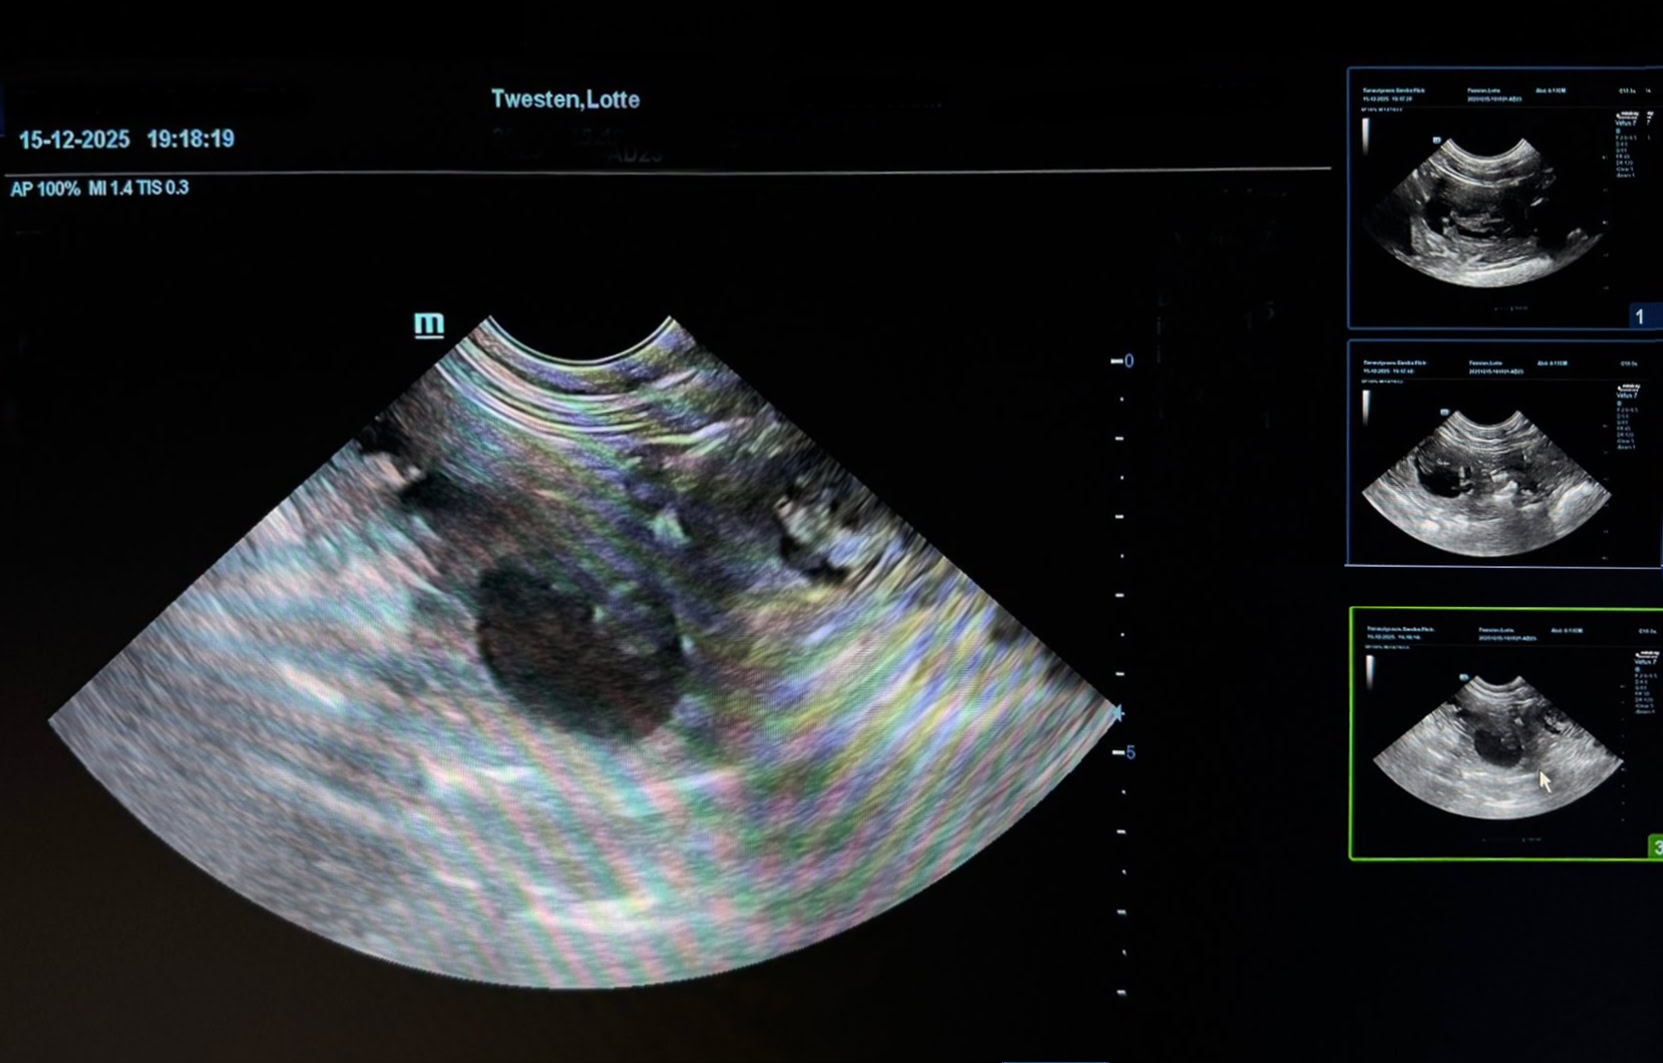

Nachdem Lotte sich zwei Tage Zeit gelassen hatte und die Geburt schließlich nahezu zum Stillstand kam, fuhren wir mit ihr zum Tierarzt. Dort wurde per Ultraschall festgestellt, dass sich ein Welpe vor den Geburtskanal gelegt hatte. Uns blieb keine andere Wahl, als die Welpen per Kaiserschnitt auf die Welt zu holen.